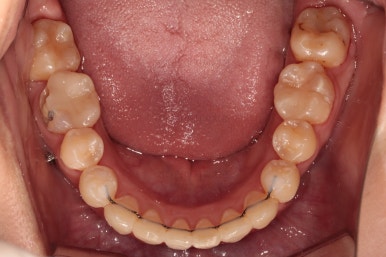

초진 시 입안의 모습입니다.

이미 썩어서 부러진 치아도 몇 개 보이고요.

많이 삐뚤어진 치아쪽은 양치가 힘들어 이미 많이 썩어 있는 상태에 덧니쪽은 잇몸도 많이 내려간 상태였습니다.

말그대로 교정치료 뿐만 아니라 전반적인 치료가 필요한 상황이었습니다.